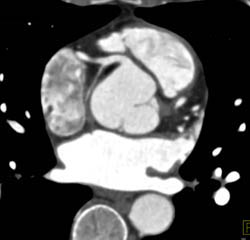

3D and MPR Sequence of Right Coronary Artery (RCA)